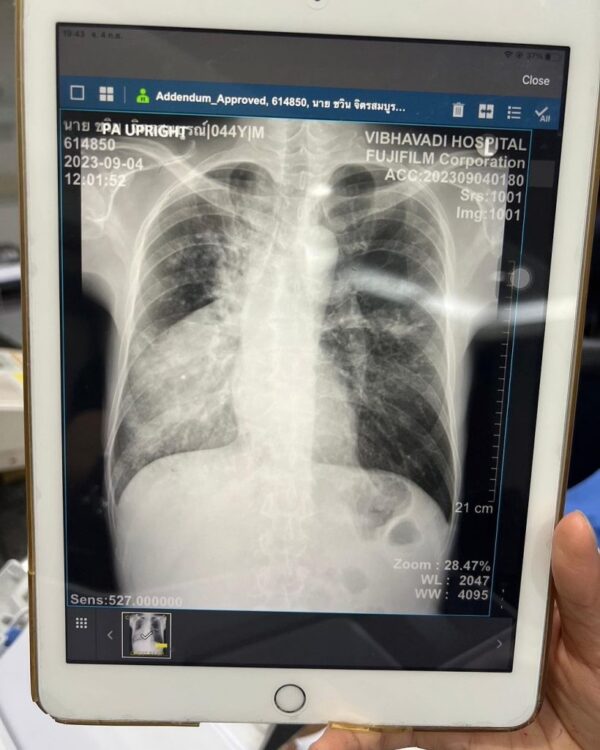

ทำเอาเพื่อน ๆ ในวงการเป็นห่วงไม่น้อย เมื่อนักร้องหนุ่มนักร้องเสียงดียุค90 อย่าง จั๊ก ชวิน จิตรสมบูรณ์ โพสต์ภาพตัวเองที่สายออกซิเจนสวมใส่ที่จมูกพร้อมภาพเอ็กซ์เรย์ปอดทั้งสองข้าง เนื่องจากติดเชื้อวัณโรคจากเพื่อนที่เสียชีวิตไปแล้ว